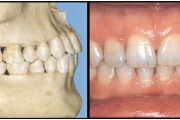

Ravijärgne seis. Jäävhammas on täielikult lõikunud.

) Röntgenülesvõte. Ülemise esimese jäävmolaari lõikumine on takistatud 2. piimamolaari tõttu

Esimese jäävmolaari ektoopiline lõikumine

Normaalse jäävhammaskonna pilt küljelt ja eest vaadatuna.